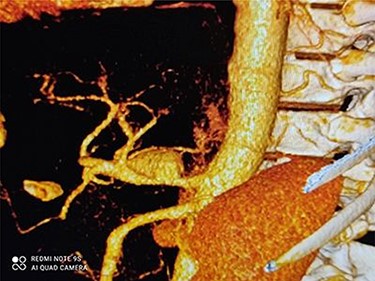

CT angiography revealed a saccular aneurysm in the right trunk of the celiac artery (42*56*59 mm) with thrombus formation lining its wall. The aneurysm lumen was patent and had a diameter of 20*21*34 mm. With a 12-mm patent neck, the aneurysm was connected to the main artery. The aneurysm was surrounded by distal branches of the left gastric, common hepatic and splenic arteries. A percutaneous angiographic intervention was suggested to the patient, and he was asked to go to NPO from midnight. After prepping and draping, a right femoral artery puncture was performed under local anesthesia, and a 6 French angiographic sheath (Arrow®) was inserted. The 6 French JR catheter (Alvision™) was extended to the aorta via a hydrophilic wire (AqWire®) and contrast media was injected, revealing a celiac artery aneurysm. The 8F*40 (Arrow®) sheath was then replaced, and the celiac artery was cannulated, and two 40*10 and 40*9 mm covered stents (Fluency™) were inserted through a stiff park wire (Amplatz Emerald). Finally, good results were obtained, with full aneurysmal coverage and distal celiac artery patency. Three days after the patient was admitted to the ward, a CT angiography revealed good results with complete coverage of the aneurysmal area and no leakage.

Figures 1 and 2 depict CAA in 3D images of CT angiography and angiography, respectively.